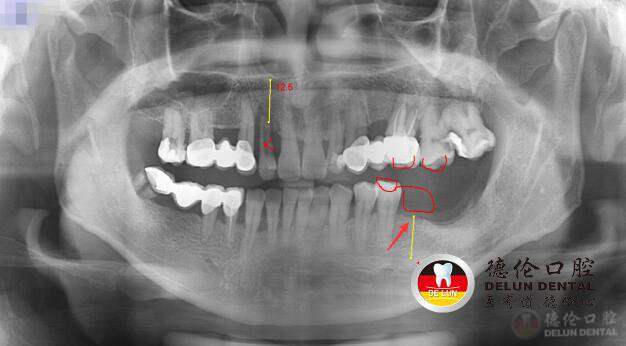

李先生术前牙齿X光片,下颌缺牙

从李先生牙齿术前X光来看,李先生牙齿情况不容乐观,上颌、下颌均有缺牙,并选择搭桥烤瓷牙作为修复方式。

我们都知道,搭桥烤瓷牙是通过将缺牙相邻两颗健康牙齿磨小,制造出“烤瓷桥”,“桥”两头是被盖上牙冠的两颗被磨小的健康牙齿,“桥”中间是一颗或多颗烤瓷牙。这种修复方式,需以损伤相邻两颗好牙为代价。

也就是说,从李先生的牙片上看,李先生已经为了修复3颗牙齿,损伤了6颗健康好齿。

此次李先生左下颌的缺牙,烤瓷牙却无法“拯救”李先生。一来做搭桥烤瓷牙需以损伤相邻的好牙为代价,二来李先生左下颌这颗缺失的牙齿无法制造出“烤瓷桥”。李先生表示,常听朋友说种植牙很好,既不用损伤健康的邻牙,也不需要像假牙那样取出来清洗。这回,李先生也想体验一把种植牙的魔力!